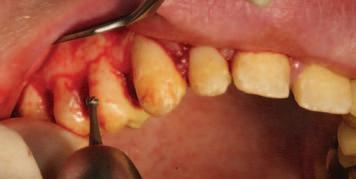

A unilateral sagittal split osteotomy was performed using piezosurgery to protect the nerve. The alveolar nerve, extending from the apical region of the left first and second molars to the mental foramen, was uncovered, and a meticulous dissection was performed to release it from the canal. Notably, rigid paste debris was observed in proximity to and within the nerve canal. The nerve exhibited signs of swelling and was surrounded by granulation tissue (Figures 4 and 5 ).

FIGURE 4: Unilateral sagittal split osteotomy.